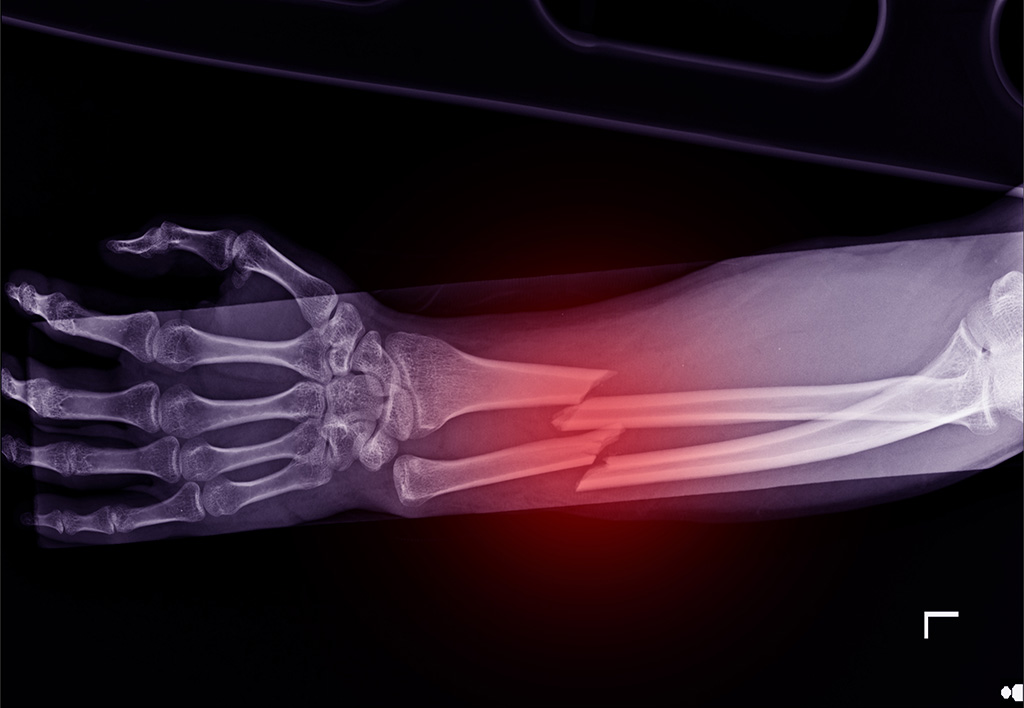

A fracture is another term for a broken bone. These two words are used interchangeably and refer to any break in the continuity of the bone. Fractures can vary widely, from minor cracks to severe breaks that disrupt the bone’s alignment. No matter the type, each requires careful evaluation and appropriate care to ensure proper healing.

Not every bone injury is a fracture. Sometimes, an impact can cause a bone contusion, which is essentially a deep bruise to the bone. While it can be painful and take time to heal, a contusion does not involve broken bone. However, the distinction isn’t always obvious. Bone contusions can mimic fractures in symptoms like swelling and pain but often require advanced diagnostic tools to confirm.

Stress fractures occur when a bone is repeatedly subjected to small amounts of force over time. Unlike fractures caused by a sudden impact, stress fractures develop gradually, often in active children participating in high-impact sports. These tiny cracks in the bone can be tricky to diagnose as they may not appear on a standard X-ray initially, requiring specialized imaging for clarity.